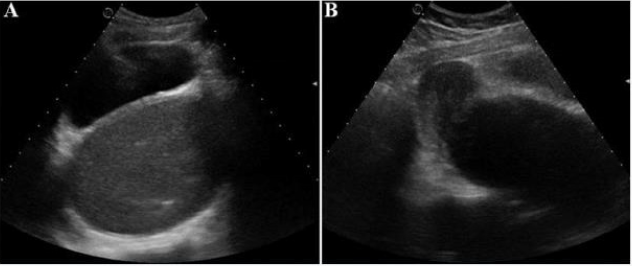

Figure 3:

A. Axial Suprapubic ultrasound: presence of a retrovesical, median, hypoechoic fluid formation containing a fine echogenic stippling

B. Sagittal section: the collection communicates at the top with the uterine cavity which is not distended.